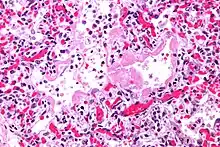

| Micrograph showing hyaline membranes, the key histologic feature of diffuse alveolar damage. H&E stain. | |

- Diffuse alveolar damage (DAD): an acute lung condition with the presence of hyaline membranes.[2] These hyaline membranes are made up of dead cells, surfactant, and proteins.[1] The hyaline membranes deposit along the walls of the alveoli, where gas exchange typically occurs, thereby making gas exchange difficult.

- The edema contributes to the deposition of a hyaline membrane (composed of dead cells, surfactant, and proteins) along the alveolar walls. Hyaline membranes are characteristic of DAD.

In order to make a diagnosis of DAD a biopsy of the lung must be obtained, processed, and examined microscopically. As described above, the hallmark of diagnosing DAD is the presence of hyaline membranes.[1] Most frequently DAD is associated with ARDS, but since there are clinical criteria (see Berlin criteria above) upon which we can diagnose ARDS, it is often unnecessary in all cases to obtain invasive biopsies of the lung. Additionally, there are limitations of the biopsy test since it is possible to sample a potentially normal area of lung even though there is DAD in the rest of the lung, resulting in a false negative.[1]